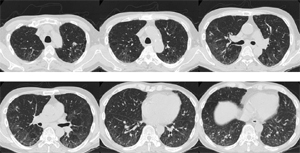

数日後という短時間で血液培養から抗酸菌が検出された→Rapidly growing mycobacterium (RGM)による敗血症と診断(図6)(図7)(図8)

抗菌薬(主にアミカシン)で加療され、肺病変は縮小

画像報告は1例のみで両肺びまん性線状影・網状影、両下葉優位の consolidation を認めたとされる